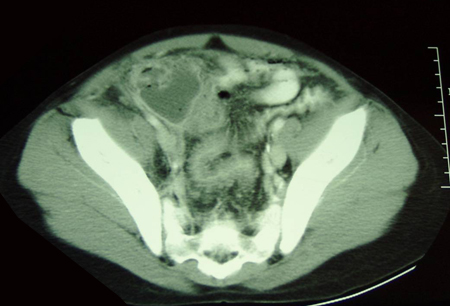

Tomografia computadorizada (TC) revelando abscesso intra-abdominal consistente com apêndice perfurado

Do acervo de Dr. KuoJen Tsao; usado com permissão